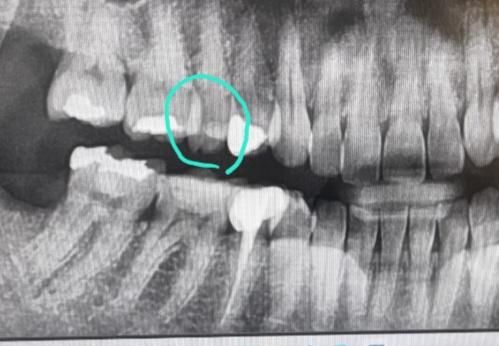

엑스레이에 저 이빨인데 자꾸 음식물이 많이껴서 오늘보니 구멍이 뚫려 있네요.. 이거 제가 전에 치료를 했던게 떨어진건가요?언제 어떤 치료했는지 언제떨어졌는지 기억도 안나요.. 엑스레이상에서 저 흰색부분은 떼운건가요? 전 이제 어떤치료를 다시 받으면 될까요 그냥 떼우면 되나요.. 알려주세요..빨리 치과를 가야 신경치료 안하겠죠?

네 흰색부분은 레진으로 예전에 떼운 것 같습니다

치과가서 검사해봐야겠으나 충치가 다소 깊어 보입니다 가급적 빨리 치과가보세요